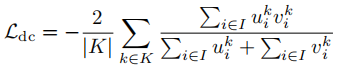

5.1 损失函数

损失函数为diceloss+交叉熵损失函数: L = L d i c e + L C E L=L_{dice}+L_{CE} L=Ldice+LCE,其中,dice loss公式如下: